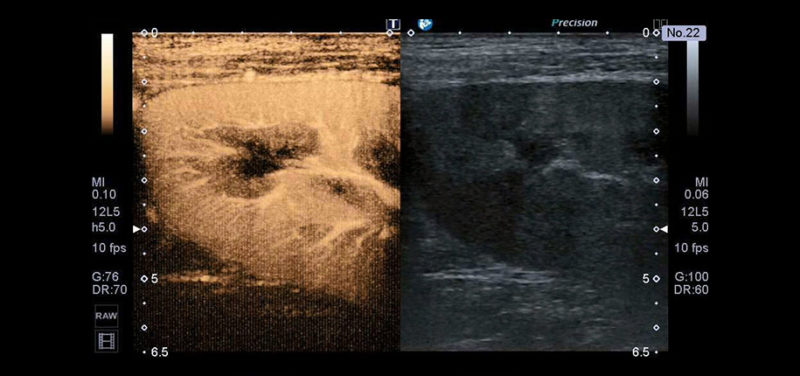

Image: This image demonstrates the blood flow to the upper pole of a kidney. The image on the right is the usual gray-scale ultrasound image of the kidney, whereas the image on the left is contrast-enhanced, showing the vessels and the perfusion of the renal tissue.

Image: This image demonstrates the blood flow to the upper pole of a kidney. The image on the right is the usual gray-scale ultrasound image of the kidney, whereas the image on the left is contrast-enhanced, showing the vessels and the perfusion of the renal tissue.